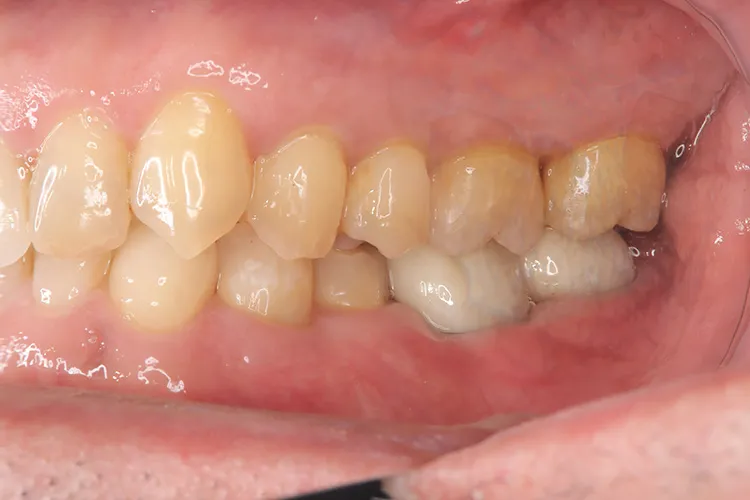

左下67 欠損に対してインプラント治療を行った症例

部分床義歯を使用していたが、どうしても慣れない上にしっかり噛むことができないためインプラント治療を希望